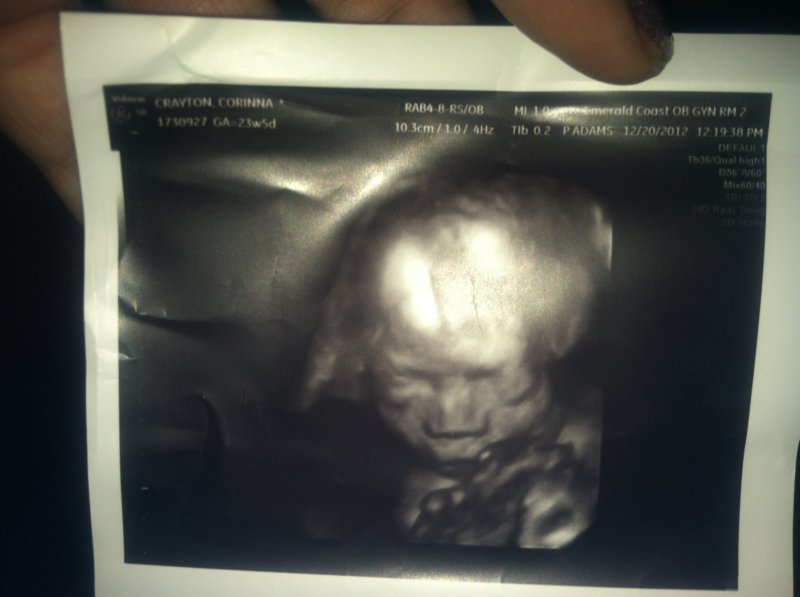

IMG_0003